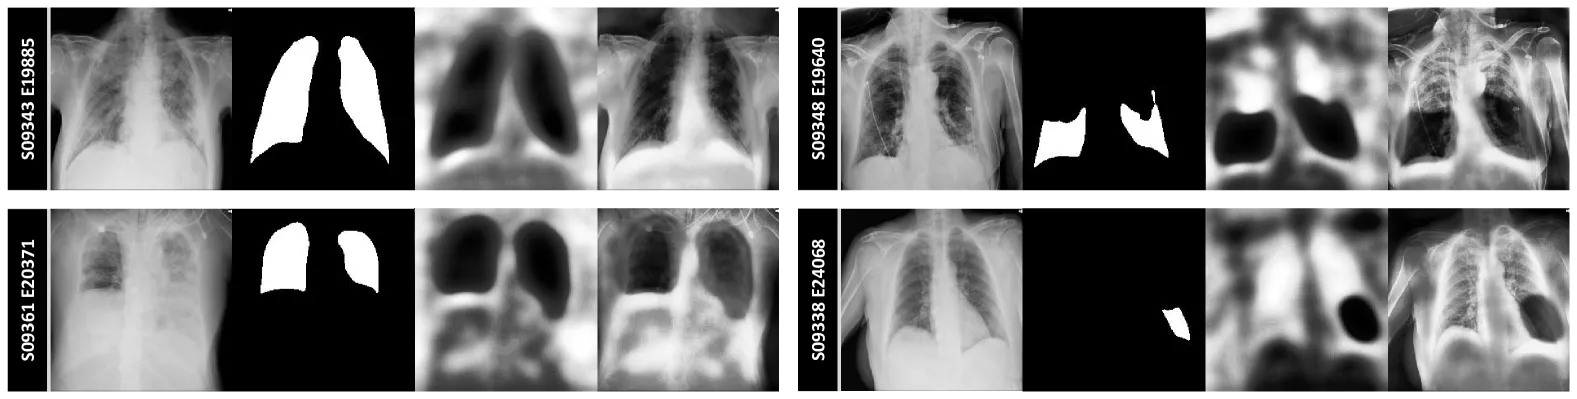

4.3. Visualization

- 학습 시에는 정답 텍스트, 추론 시에는 생성된 텍스트를 사용하게 되면서 분할 성능에 일정한 영향을 준다.

- 생성된 리포트의 정확도가 낮을 경우, 성능 저하가 소폭 있지만 안정적임

- 어텐션 맵 분석 결과, 모델은 병변 부위에 정확하게 주목하며 분할에 중요한 집중 패턴을 보임